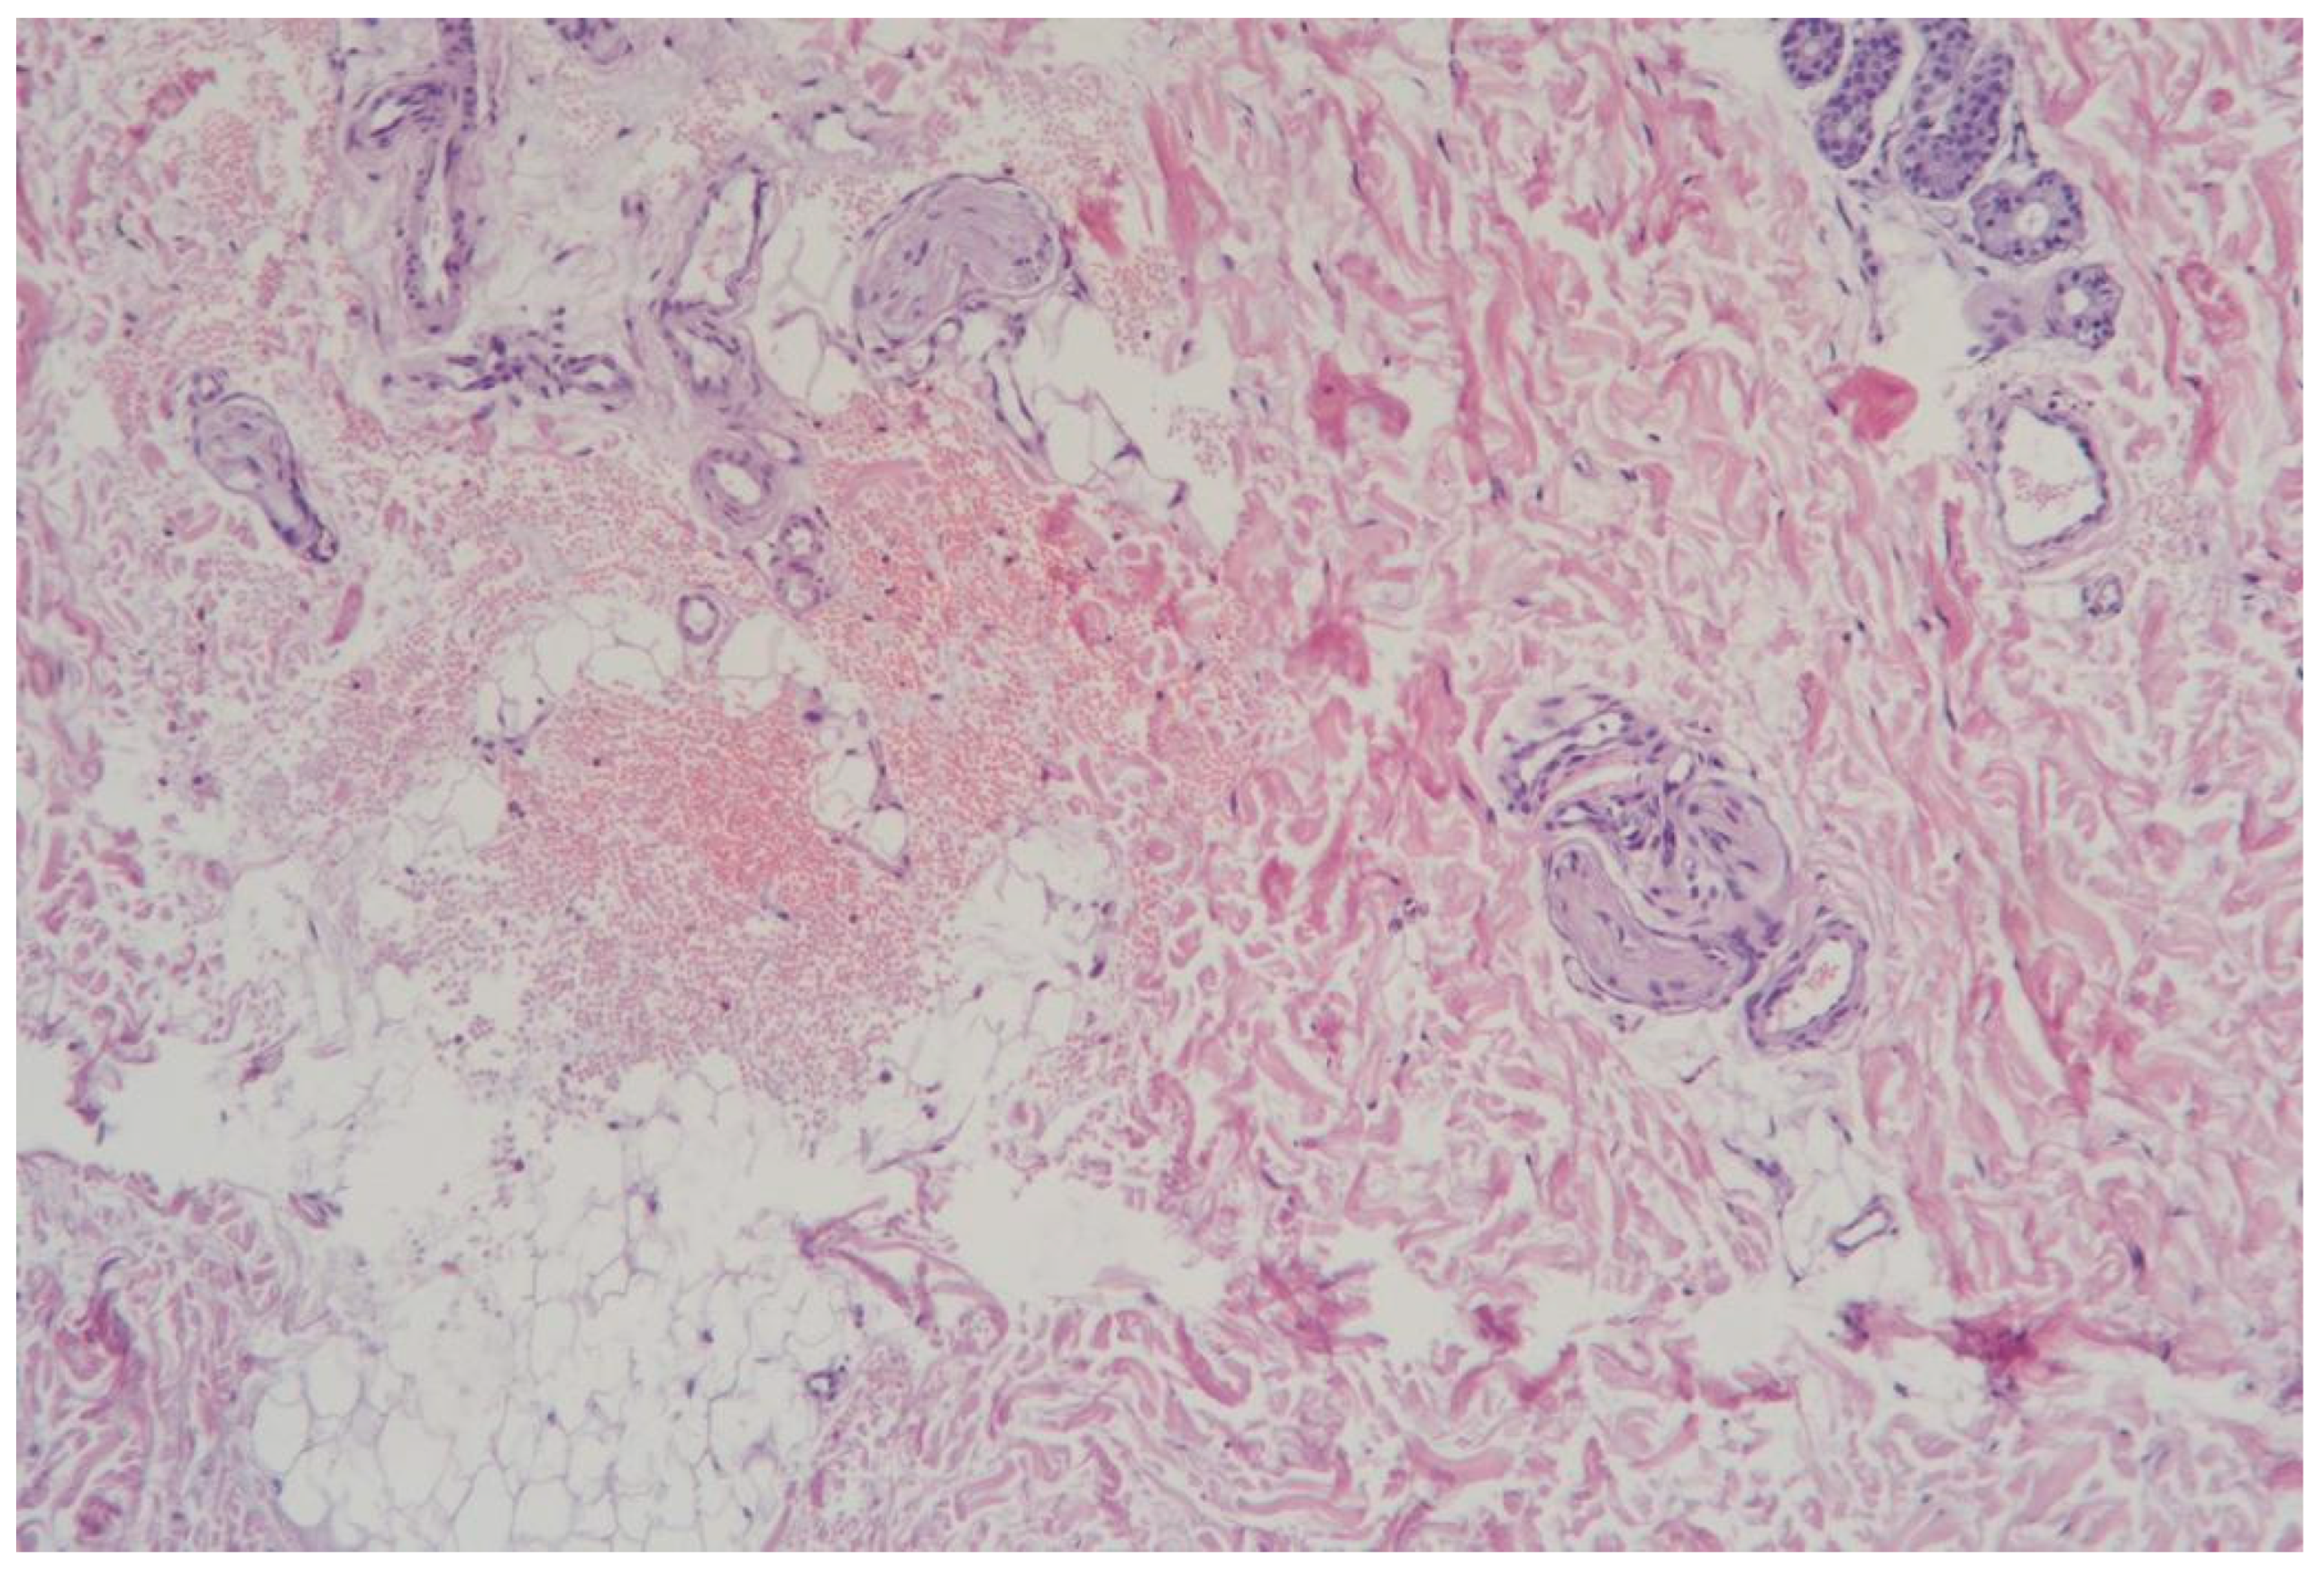

3.1.1. Clinical Case 1: Soft Tissues in the Dissection Area, Scar 10 W (See Figure 2)

Description: The histological examination revealed total necrosis of the epidermis and dermis, with the formation of a demarcation zone heavily infiltrated by polymorphonuclear leukocytes. The infiltrate extended into the subcutaneous adipose tissue. The vessels within the necrotic zone were coagulated, while those in the underlying tissues were markedly dilated. Small diapedesis hemorrhages were noted. The skin appendages in the underlying tissues remained intact, and the collagen fibers were preserved.

Figure 2. Skin changes in Rat 1 on the 7th day after exposure to the thulium laser at 10 W, 65 Hz. H&E staining, 10× objective magnification.